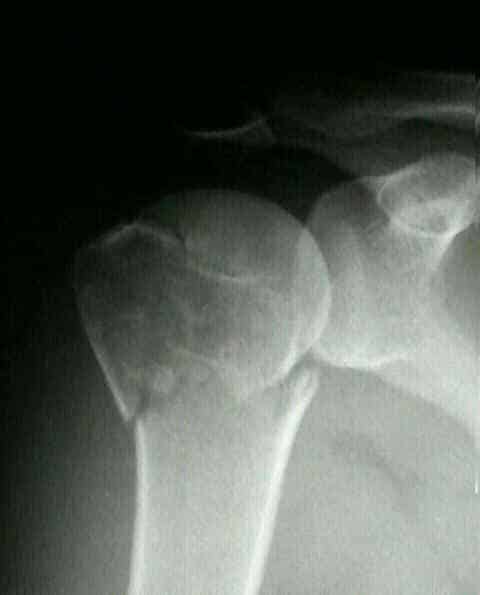

При обращении пациента в травматологический пункт врач проводит осмотр поврежденной конечности, выясняет обстоятельства травмы и уточняет жалобы. После этого для определения точного диагноза травматолог назначает дополнительные исследования. Диагностика позволяет различить перелом шейки от вывиха. Если наблюдаются нарушения чувствительности на наружной стороне плеча и отвисание руки, это может указывать на повреждение подкрыльцового нерва.

Наиболее информативным методом является рентгенография. Снимки делают в двух проекциях: аксиальной, когда изображение получается сверху вниз через подкрыльцовую ямку, и в прямой. При необходимости для более детального анализа травмы может быть назначена компьютерная томография.

Внутрисуставные переломы подтверждаются с помощью ультразвукового исследования. Снимки плечевой кости в аксиальной проекции позволяют выявить наличие боковых смещений отломков. Рентгеновские изображения помогают диагностировать и различать вколоченный перелом плечевой кости от невколоченного.